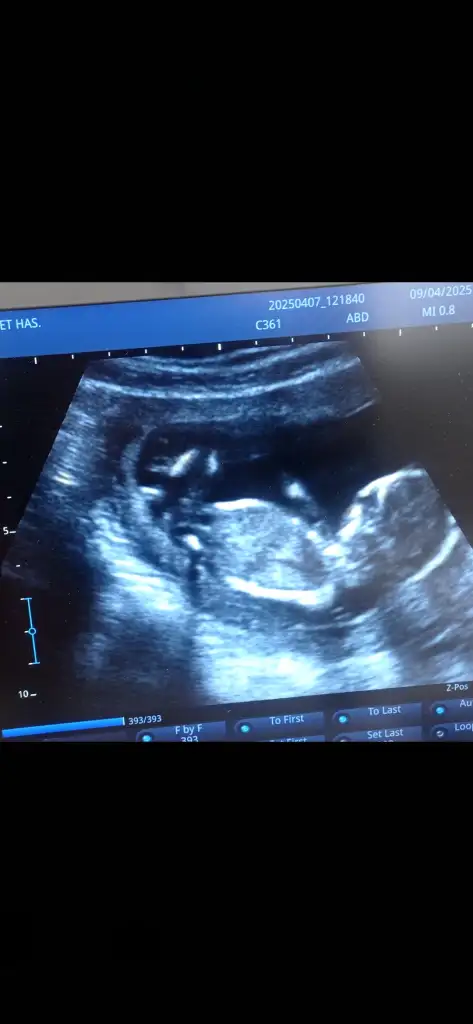

kızAy rica etsem banada bakar mısınız 12+1 ultrason resmi vermedi doktor videodan ekran görüntüsü aldım